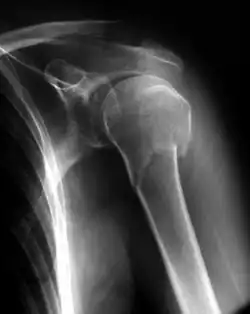

Radiografia que mostra uma fratura abaixo da cabeça do úmero.

As fraturas podem ser classificadas de acordo com vários critérios.